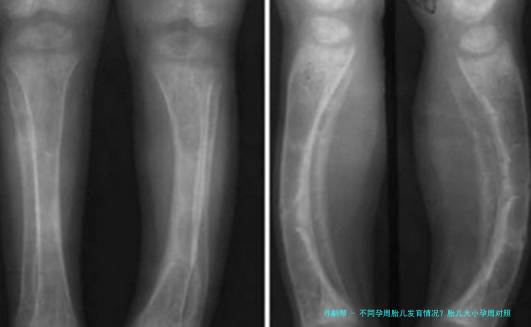

不同孕周胎儿发育情况?胎儿大小孕周对照